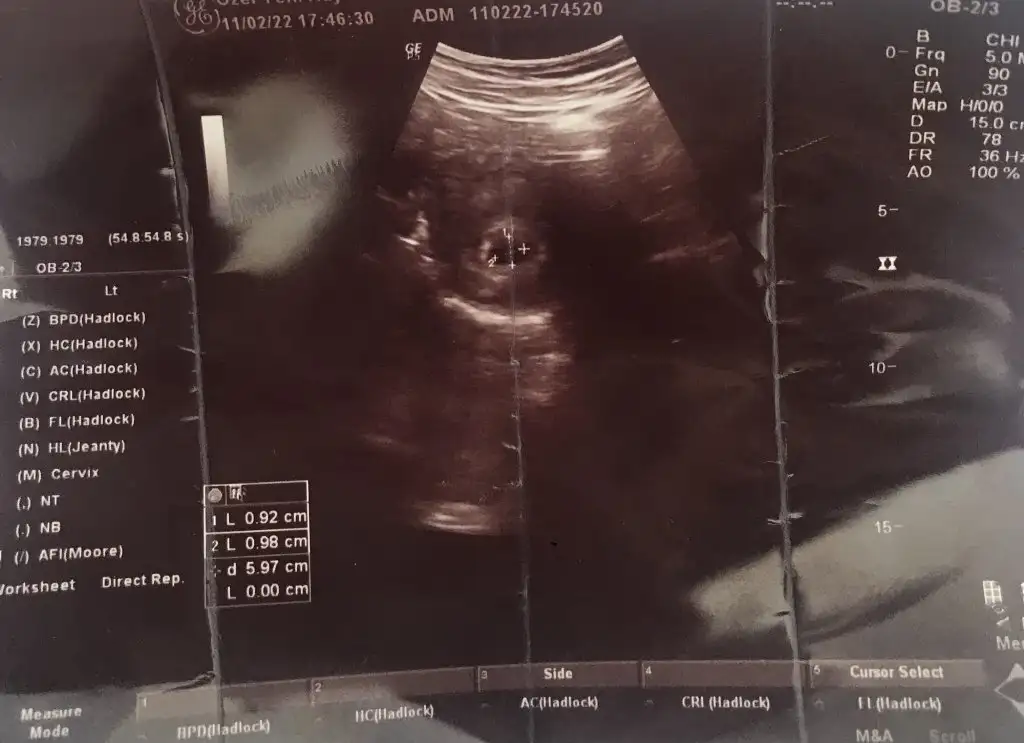

Bunlardan başka bir şey yok ki beybisi, hastane ve benim adım dışında.Ay minnoş yaakuzum ultrason kagitlarimiz farklı tam halini bi çekip atsana, kıyıda köşede ga veya crl yazan bi yer yok mu

Baksana kuzu benim sağ altta yazıyor bende internetten baktım anlamlarına, crl bebek boyu, ga haftası, edd tahmini doğum tarihiymis bende ordan biliyorum. Ama seninki ingiliççe pek anlamadımBunlardan başka bir şey yok ki beybisi, hastane ve benim adım dışında.

Ama ultrason kağıdının altında da yazıyor, sağ alt köşede hem doğum tarihi, hem haftan hemde bebisin boyu